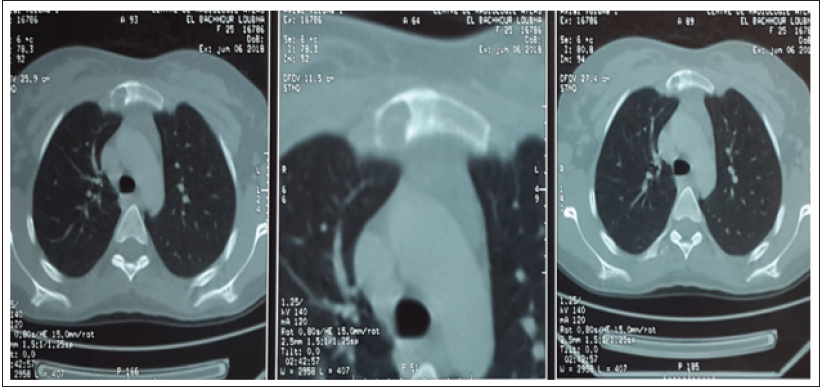

She is Miss S.A, aged 18, with no notable pathological history, including no tuberculosis or concept of tuberculous contusion, which has had a parasternal right swelling for a month. The examination of the swelling found a parasternal right mass just below the clavicle opposite the first intercostal space, painful on palpation, with redness, without cutaneous fistulization. An initial chest x-ray was requested returning without abnormality, in particular no lysis opposite, or associated parenchymatous involvement, with an infectious assessment negative made of a blood cell parameters and C- reactive protein, A thoracic computed tomography was performed objectifying an osteolytic lesion with intraosseous sequestration at the right super-lateral part of the sternum (Figure 1), associated with infiltration of the soft tissues and two abscesses, the first at right intercostal muscle level, and the second in the anterior parietal area (Figure 2). Flattening of the swelling was performed in the patient, with bacteriological and histological samples of the abscess. The direct examination and the culture of the pus came back negative. However, the molecular study of the collection by GeneXpert objectified a tuberculosis. The anatomopathological study revealed a granulomatous lesion, but without caseous necrosis. The patient was put on antibacillary treatment with good clinical progress.

Figure 1: Osteolytic involvement with intraosseous sequestration at the right superior-lateral part of the sternum.